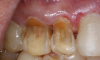

Lifestyle Modifications

In offering preventive instructions to the patient, the health practitioner, be it a physician, dentist, or even dental hygienist, must identify the causal factors of erosive tooth wear, which should be followed by instruction in modifying or avoiding these factors. To address dietary causes, ideally abstinence from acidic foods and drinks would be recommended for prevention of dental erosion. However, if the patient cannot comply, modifying such eating and drinking habits might also suffice. Modifications to reduce the frequency of intake and contact time of acids may slow the progression of dental erosion considerably. The duration of acid contact to the dentition can be decreased through controlled intake whereby patients do not hold or swish acidic beverages in the mouth and avoid slow ingestion of such drinks. Figure 12 is an example of the clinical erosion of enamel of a patient who often sipped and held soda drinks in his mouth in high frequencies throughout the day. This habit promoted loss of enamel and dentin in the facial and incisal surfaces of the patient's upper incisors. He was made aware of how this habit contributed to the tooth pathology and was educated on dietary and habit changes in an effort to reduce tooth destruction.

Fig 12. Eroded facial surface with loss of enamel and dentin in maxil- lary incisors in a patient who was a habitual soda drinker.

Figure 12